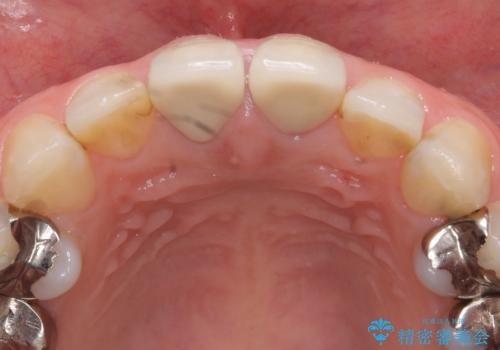

- 上顎の前から2番目の歯の古い樹脂をセラミックにしたいといらっしゃった方の症例です。

古い樹脂を除去後、オールセラミッククラウンによる補綴を行いました。

今回用いたオールセラミッククラウンはジルコニアフレームという白い素材の上にセラミックを盛っているため、審美性が非常に高いのが特徴です。

また、ジルコニアは人工ダイヤモンドの材料にも使われているほど高い強度を持っており、そのためオールセラミッククラウンは審美性だけでなく、奥歯やブリッジの補綴も可能とするクラウンです。